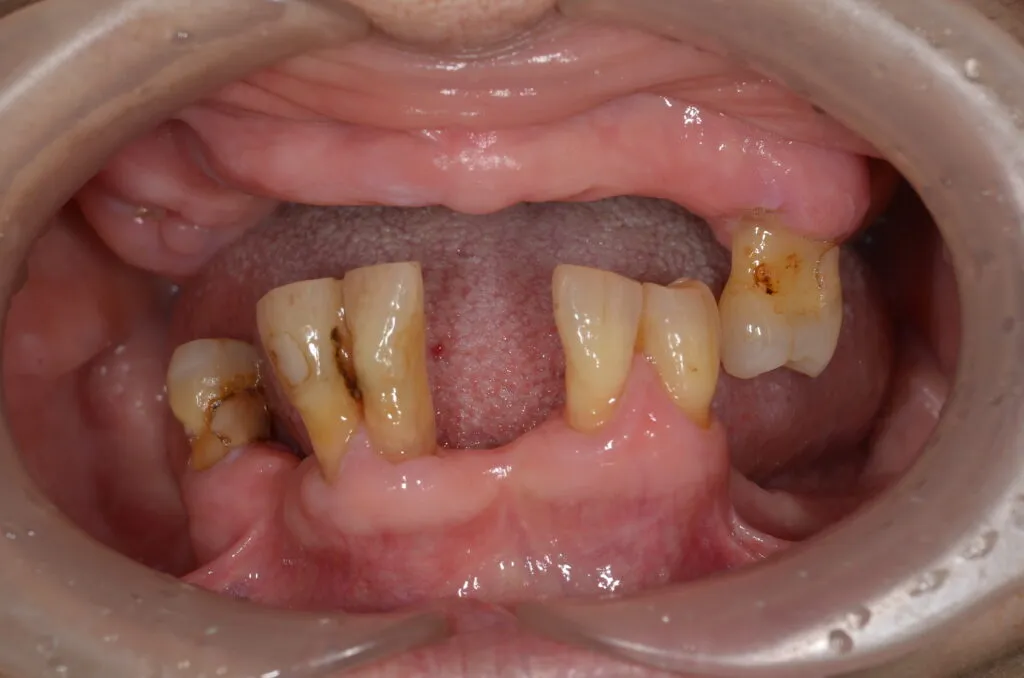

義歯で一番難しいのは総入れ歯で、特に下が総入れ歯になると多くは骨が無くなっているため、入れ歯が安定せずに、食べられないという悩みも多く聞きます。そのため、義歯作製に多くの特殊な知識・技術が必要となります。

当院では、下あごにピッタリと吸着し、リンゴや堅い煎餅でもしっかりと噛める快適な義歯をご提供いたします。

固いせんべいやリンゴ丸かじりも夢ではない!?

義歯が出来上がり、噛めることを実感された患者さんの表情を見れた瞬間が何より嬉しいです。

上下総入れ歯でも、固くて有名な草加せんべいやリンゴ丸かじりできるようになられるかたも多くいらっしゃいます。